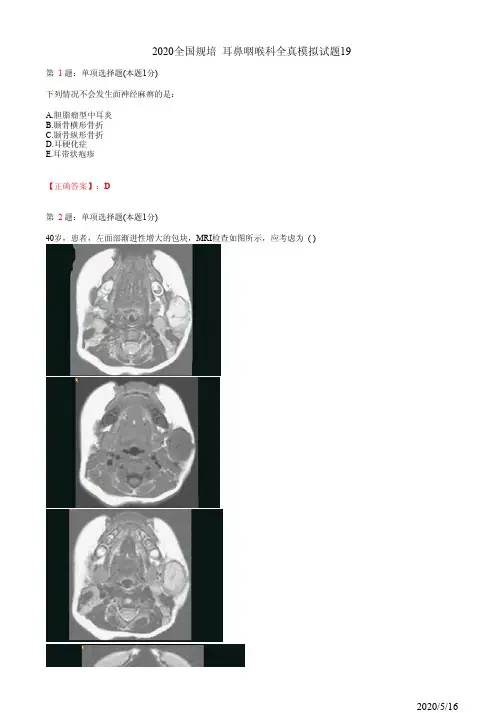

2020全国规培 耳鼻咽喉科全真模拟试题6

第 1题:单项选择题(本题1分)

男,21岁,6个月前头外伤,伤后右鼻腔流清水,2个月前曾高热、头痛、颈硬。

检查:右鼓膜完整,混浊。

传导性聋,声导抗B型曲线,本例最可能的诊断是

A.外伤性脑脊液耳鼻漏

B.颞骨岩部骨折

C.外伤性脑脊液鼻漏

D.前颅底骨折伴感染

E.过敏性鼻炎合并化脓性脑膜炎

第 2题:单项选择题(本题1分)

颞骨组成部分中不正确的是